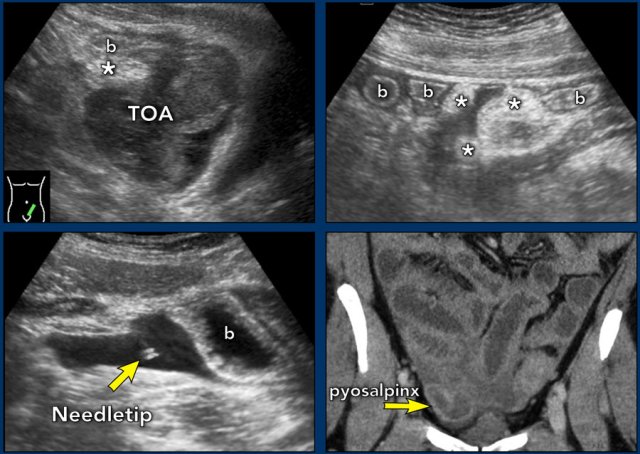

TOA case 3

Large

left sided TOA with air-configurations.

This is a rare finding in TOA, successful

treatment with only antibiotics.

TOA case 4 (infected endometriotic cysts)

These images are of a 29-year old woman, suspected for appendicitis. CRP 185, WBC 17.

US shows a normal compressible appendix, thereby excluding appendicitis.

Large, thick-walled, septated cystic structures, filled with debris-like material, were found on both sides of the uterus (ut.), touching each other posteriorly (“kissing ovaries”).

This is somewhat suspect for bilateral infected endometrotic cysts.

The patient was treated with antibiotics and laparoscopic drainage.

There was a protracted course, but eventually regression of the abnormalities.

Pyosalpinx

case 1

these images are of a young woman with pain in the RLQ for two days and CRP 170 and WBC 14.

US respectively

TVUS shows tortuous, thick-walled tubular

structure right of the uterus (ut.), in combination with the CRP, typical for a

pus-filled Fallopian tube (pyosalpinx).

This

patient was successfully treated with antibiotics but had recurrent episodes.

For this reason she underwent

a tubectomy three years later.